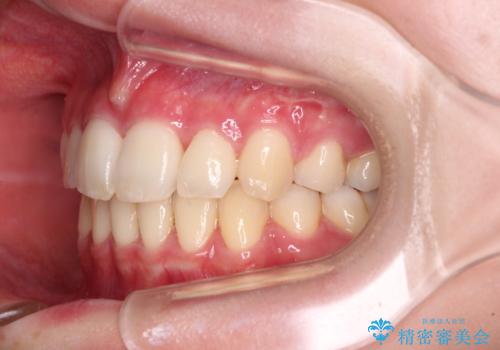

治療途中で転院 抜歯矯正の仕上げ治療

- 地元で抜歯治療を行っている途中、東京へ転職したため治療を継続して欲しいとのことで来院された患者様です。

出っ歯を抜歯矯正にて治療をしていらっしゃいましたが、抜歯スペースが少し残っていたため、閉じて歯列を仕上げていくこととしました。